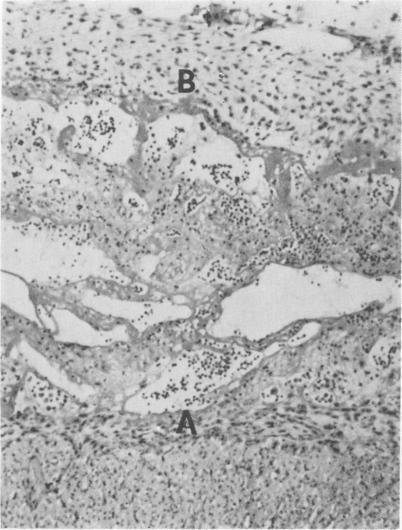

Forty gnotobiotic pigs from six litters were exposed orally to Escherichia coli 083:K.:NM at 69 to 148 hours of age, while 17 pigs from the same litters served as unexposed controls. Clinical signs of infection included fever, anorexia, diarrhea, lameness, and reluctance to move.Eighty-four percent of the exposed pigs in four litters died, while only 13% in two litters died. Gross and microscopic lesions included serofibrinous to fibrinopurulent polyserositis in 96% of the exposed pigs in four litters and 33% of the exposed pigs in two litters. A few pigs had gross and/or microscopic lesions of arthritis. Escherichia coli was routinely isolated from the serous and synovial cavities of infected pigs.Anti-hog cholera serum administered orally as a colostrum substitute gave partial protection against E. coli infection.

来自六窝的40只无菌猪在69至148小时大时经口接触大肠杆菌083:K.:NM,而来自同一窝的17只猪作为未接触的对照。感染的临床症状包括发热、厌食、腹泻、跛行和不愿活动。四窝中84%的接触猪死亡,而两窝中只有13%的猪死亡。大体和显微镜下病变包括四窝中96%的接触猪和两窝中33%的接触猪出现浆液纤维蛋白性至纤维蛋白脓性多浆膜炎。少数猪有关节炎的大体和/或显微镜下病变。从感染猪的浆液和滑膜腔中常规分离出大肠杆菌。口服作为初乳替代品的抗猪霍乱血清对大肠杆菌感染有部分保护作用。